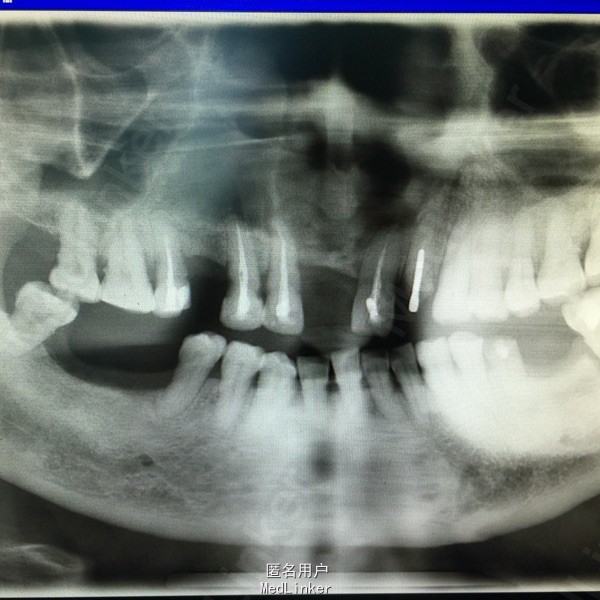

随访:患者自行用盐水冲洗创口,每半年复诊一次,全景牙片示:囊腔逐步减小,骨质形成。二年后复查囊腔大小约1x0.5cm。局部行囊肿挖除术。 讨论:囊肿开窗减压术,最大的保存愚者骨组织、患区牙保留。但需有良好的医从性。